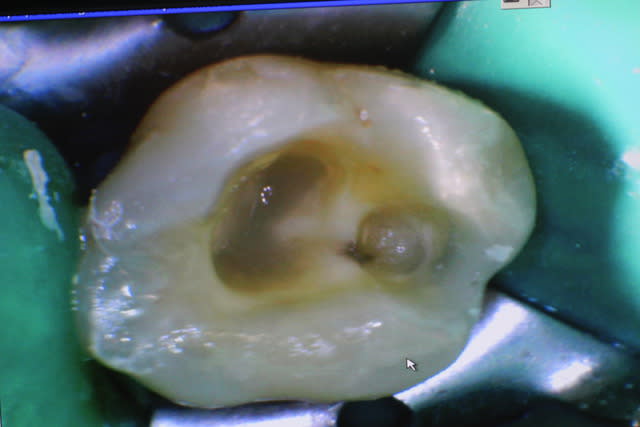

un cas réalisé depuis : une endocouronne réalisée la semaine dernière sur une nécrose d'origine paro ,

surfaçage + laser pendant la cuisson , a voir dans le temps...

1h d'endo + CVI

prep : 10 minutes

paramétrage usinage 10 minutes

usinage + cuisson 35 minutes => surfaçage arcade complète + essayage du biscuit

pose 10 minutes

rdv de 2h30